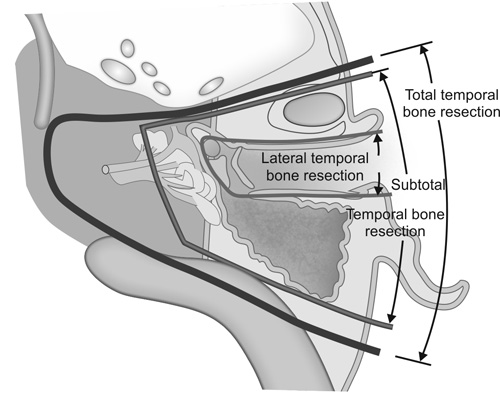

Advanced otology encompasses complex ear and skull base conditions requiring specialized surgical care. We offer cochlear implants and bone conduction implants for hearing loss, treat acoustic neuroma and temporal bone tumors, and perform stapes surgery for otosclerosis. Our team also manages cholesteatoma, superior canal dehiscence, and other advanced ear conditions. Select a topic below to learn more.